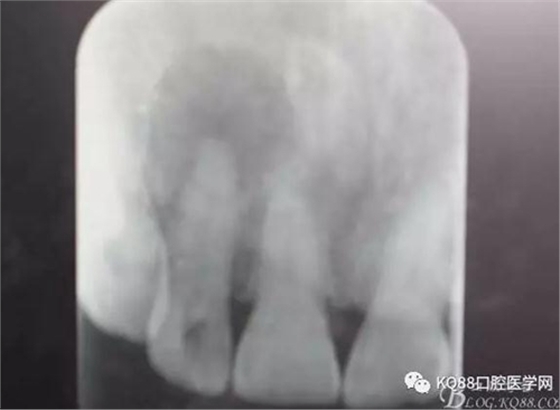

圖1.患者在根管術(shù)前的根尖片影像檢查:12有開(kāi)髓孔,根尖有橢圓形陰影。